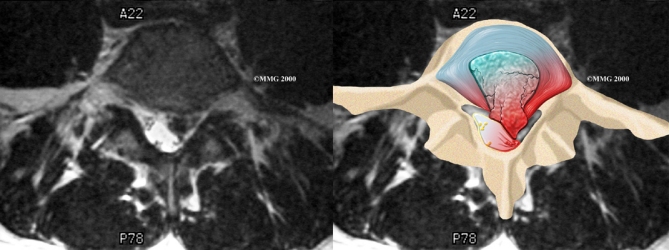

Herniation occurs when the nucleus in the center of the disc pushes out of its normal space. The nucleus presses against the annulus, causing the disc to bulge outward. Sometimes the nucleus herniates completely through the annulus and squeezes out of the disc.

Although daily activities may cause the nucleus to press against the annulus, the body is normally able to withstand this pressure. However, as the annulus ages, it tends to crack and tear. It is repaired with scar tissue. This process is known as degeneration. Over time, the annulus weakens, and the nucleus may begin to herniate (squeeze) through the damaged annulus. At first, the pressure bulges the annulus outward. Eventually, the nucleus may herniate completely through the outer ring of the disc.

Herniation causes pain from a variety of sources. It can cause mechanical pain. This is pain that comes from the parts of the spine that move during activity, such as the discs and ligaments. Pain from inflammation occurs when the nucleus squeezes through the annulus. The nucleus normally does not come in contact with the body's blood supply. However, a tear in the annulus puts the nucleus at risk for contacting this blood supply. When the nucleus herniates into the torn annulus, the nucleus and blood supply meet, causing a reaction of the chemicals inside the nucleus. This produces inflammation and pain. A disc herniation may also put pressure against a spinal nerve. Pressure on an irritated or damaged nerve can produce pain that radiates along the nerve. This is called neurogenic pain.

When more information is needed, your doctor may order magnetic resonance imaging (MRI). The MRI machine uses magnetic waves rather than X-rays to show the soft tissues of the body. It gives a clear picture of the discs and whether a herniation is present. Like the CT scan, this machine creates pictures that look like slices of the area your doctor is interested in. The test does not require special dye or a needle.